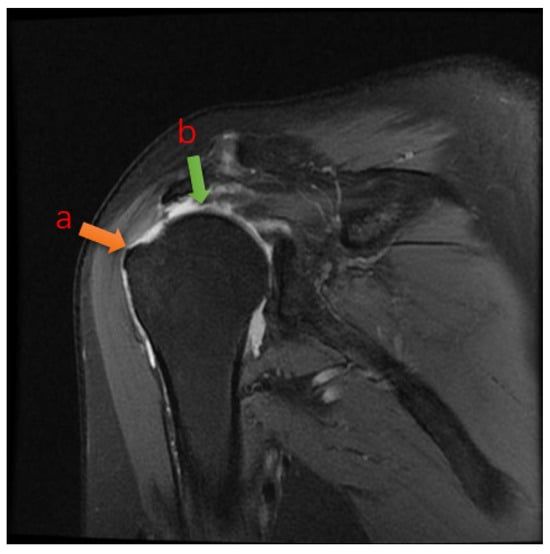

In the clinical diagnosis of rotator cuff tears nowadays, doctors often need to take a close look at multiple MRIs of the shoulder and combine them into a coherent sequence of MRIs to determine whether the area of the lesion is an effusion or a tear [4], and to measure the length of the tear with calipers to give the grade of the tear (Figure 1). The AI diagnostic method proposed in this paper can assist doctors to greatly improve the diagnostic efficiency, which has many advantages over traditional clinical diagnosis.

2.2. Image Acquisition: Ocor T2 fs Sequence

The data used in this study were MRI scan sequence images of patients (device GE HealthCare, 3.0T MR750 WIDE, GE HealthCare, Beijing, China). Each sequence consisted of 15~20 2D images. The size of the images was 320 × 224 (pixel), the field of view (FOV) was 16 × 16 (cm), the thickness was 3 mm, and the interval between images was 0.5 mm [5]. For each patient, it is often necessary to take multiple sequences because of the problem of moving during image acquisition, from which the most clearly imaged set of sequences was then selected as the data for training. Figure 1 shows examples of the workflow.

Figure 1. A typical tear image of Ocor T2. The arrow shows that the tendon is retracted from point a to point b after rupture, and the joint fluid-filled area is visible in the highlighted area between point a and point b. The joint fluid-filled area is the tear region.